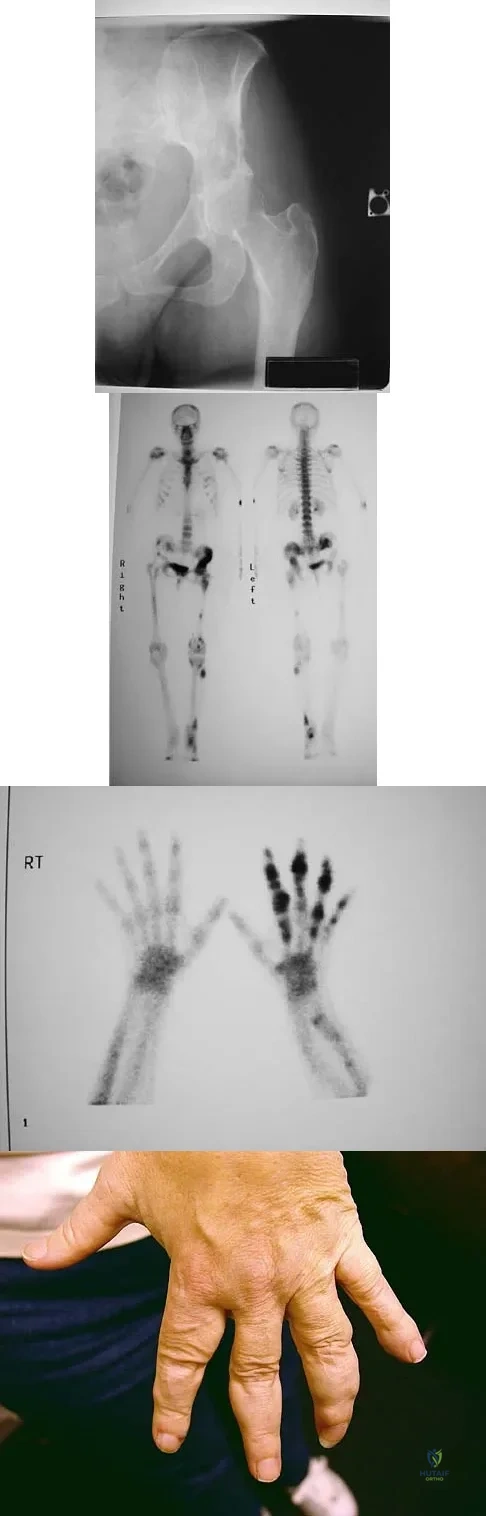

Figure 15a shows the radiograph of a patient who has a chondrosarcoma of the acetabulum. Bone scans are shown in Figures 15b and 15c. Numerous soft subcutaneous masses are present. A clinical photograph of the hand is shown in Figure 15d. What is the most likely diagnosis?

Explanation